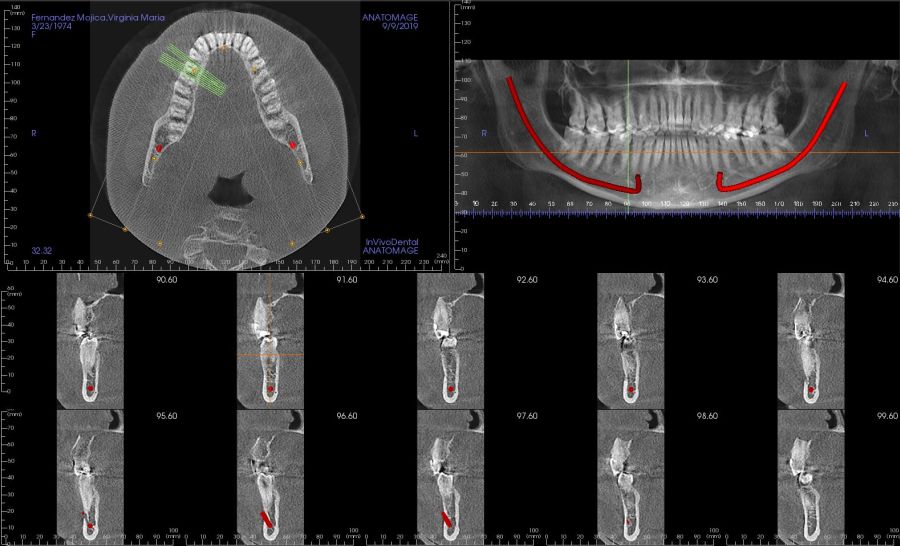

Presentamos el caso de una paciente de 47 años que acude al servicio de cirugía maxilofacial por dolor en el área sinusal derecha en Junio de 2020. Se realizó una radiografía panorámica en la que se observó una imagen sospechosa en la zona del primer cuadrante. Dichos hallazgos se confirmaron con la realización de una tomografía axial computarizada (TAC) facial y una resonancia magnética en las que se identifica una extensa lesión tumoral que ocupaba el seno maxilar derecho e infiltraba el suelo de la órbita derecha y fosa nasal derecha (Figuras 1, 2 y 3). Tras la realización de una biopsia, se confirmó la presencia de un carcinoma adenoide quístico. De este modo, se planificó la extirpación quirúrgica y la fijación mediante placas preformadas sobre un modelo impreso en poliamida (Figura 4).